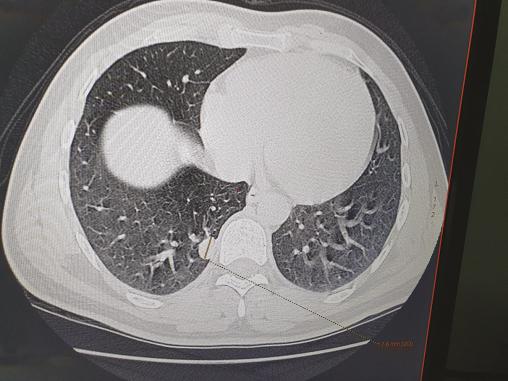

Cet homme de 35 ans, sans antécédents particuliers, avait depuis un mois une toux sèche avec une fièvre, des sueurs nocturnes, une asthénie et un amaigrissement de 10 kg. À l’examen, on notait des conjonctives décolorées, une splénomégalie et des adénopathies sous-mandibulaires. La biologie montrait une pancytopénie, un syndrome inflammatoire biologique, un taux de prothrombine bas (53 %). Sur la tomodensitométrie (TDM) thoracique, on notait un nodule pulmonaire excavé médiobasal droit (fig. 1 ). Des corps de leishmanies intra- et extramacrophagiques étaient trouvés au médullogramme (fig. 2 ). Le patient était traité par antimoniate de méglumine (Glucantime) à raison de 3 g/j pendant vingt jours ; sur la TDM de contrôle cinq mois après la guérison, le nodule pulmonaire s’était densifié (fig. 3 ).